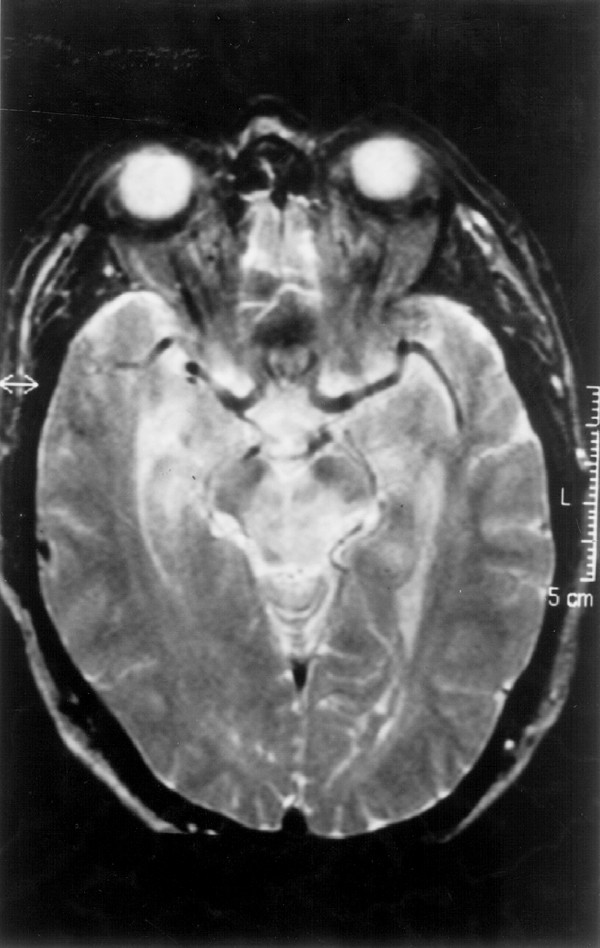

A 48-year-old man was diagnosed of Ph+, bcr/abl/ CML in the first chronic phase in April 1998. After therapy with hydroxyurea, an allogeneic transplantation was carried out in October 1998 using his HLA-identical sister's G-CSF-mobilised PBPC after CD34/ positive selection. Conditioning included high-dose cyclophosphamide and fractionated total body irradiation, and CsA (300 mg/day) was given for GVHD prophylaxis. Streptococcus sanguis sepsis developed on day +9 and was successfully treated with piperazilin-tazobactam. Platelet (>25×109/l) and neutrophil (>0.5×109/l) recovery were documented, respectively, on days /11 and /15. Neither symptoms nor signs of GVHD were noted during the post-transplant period. On day +37 fever reappeared; blood and urine cultures were negative and amphotericin was started. A thoraco-abdominal CT scan, a hepatosplenic ultrasound exam and a CT scan of the paranasal sinuses were normal. The creatinine plasma levels increased up to 261 μmol/l prompting discontinuation of amphotericine; CsA was tapered and ultimately discontinued on day +54, leading to a rapid and definitive normalisation of renal function by day +57. Hypertension developed and was sequentially treated with nifedipine, captopril and IV labetolol without adequate control. On day +57, speech tremor and weakness were noted; the sodium level was normal (139 mmol/l). On day +60, diplopia appeared; a cranial CT scan was normal and the CSF was acellular with a normal glucose and protein content; serum sodium levels were normal (137 mmol/l). On day +64 the fever disappeared but bradipsychia developed, the conscience level diminished, and dysarthria and left supranuclear facial paresis were evident; hyponatremia (123 mmol/l) with normal renal function was recorded. That day, an MRI examination (Figures 1 and 2) disclosed multiple lesions in the basal ganglia on both sides, in the right putamen, the left globus pallidus and right subthalamic region extending to the mesencephalic peduncles, pons and middle cerebellar left peduncle; lesions were also seen in the subcortical and deep white matter bifrontal lobes and the left external capsule presenting as high-intensity areas in T2-weighted images, with moderate low intensity in T1-weighted images, and without mass effect; all these multiple supra-infratentorial lesions strongly suggested CEPM. The patient's condition worsened on day +65, with dysphagia, tachypnea and increased respiratory effort with normal O2 saturation; this picture, attributed to pseudobulbar palsy, prompted the initiation of mechanical ventilation for 4 days. After extubation the patient continued afebrile, his blood pressure was normal, and the neurological signs and symptoms gradually disappeared. A repeat MRI on day +84 was normal. Blood counts at discharge on day +88 showed Hb 9.6 g/dl, WBC 4.0×109/l (55% segmented neutrophils, 8% eosinophils, 1% basophils, 28% lymphocytes and 8% monocytes), platelets 88×109/l, and normal sodium and creatinine levels. CsA was not reintroduced. The patient remains free of symptoms attributable to CEPM and in molecular remission of CML 28 months after allogeneic haematopoietic transplantation. Figure 3 displays a time-course chart with the main clinical and laboratory features of this case.